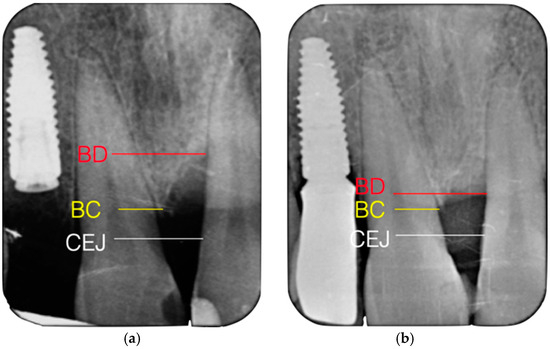

2.4. Radiographic Evaluation

3.2. Clinical and Radiographic Results